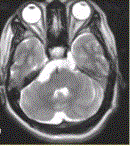

问题 患者女,41岁。右侧面肌抽搐。MRI显示如下图。 关于表皮样囊肿与蛛网膜囊肿的鉴别诊断,正确的是

选项 A.表皮样囊肿为CSF样囊性肿块,包绕邻近血管、神经 B.表皮样囊肿形态不规则,肿瘤沿蛛网下腔蔓延,“见缝就钻”为其特点 C.蛛网膜囊肿FLAIR、DWI低信号 D.表皮样囊肿边界清,形态规则 E.蛛网膜囊肿FLAIR、DWI高信号 F.表皮样囊肿FLAIR、DWI高信号

答案 ABCF